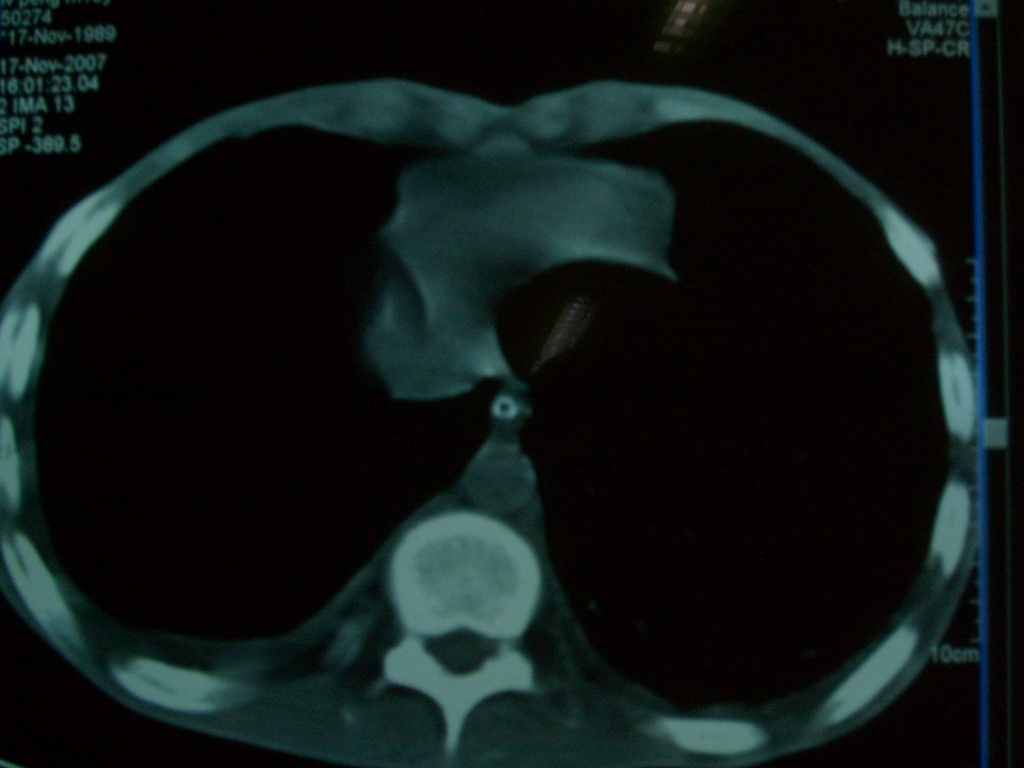

标题: CT10510:男.18岁,咳嗽咳痰两月.(有病理) [打印本页]

标题: CT10510:男.18岁,咳嗽咳痰两月.(有病理)

双肺布满大片状实变及网格状结节影,内参杂大小不等的气囊及空气支气管征,心脏增大。考虑:1 全身结缔组织疾病—系统性红斑狼仓?2 肺泡蛋白沉积症合并感染!

双肺布满大片状实变及网格状结节影,内参杂大小不等的气囊及空气支气管征,双侧胸膜腔少量积液,双下肺近膈面透亮度尚可,病人较年轻,病变较重(不知为什么上胃管?)考虑:1.胶原病肺部改变,2.组织细胞病x。结合实验室检查。

首先考虑组织细胞x病。两肺中上肺野多发囊腔,中下肺野内见多发小结节,并可见肺间质增厚。患者是男性,年龄较小。胶原性病变比较多见的类风湿、系统性红斑狼疮和硬皮病临床和影像均不是很支持,类风湿和系统性红斑狼疮的肺部表现最常见的是胸腔积液,硬皮病可见食管的扩张。

肺内多发斑片状、结节状、融合大片状及网格状影,多发薄壁空腔影,胸膜肥厚,纵隔、气管右移,考虑ⅲ型肺结核,多发空洞,继发肺间质纤维化。

双肺结核并播散.患者以肠梗阻入院,手术为肠结核.术后咳嗽做ct检查.